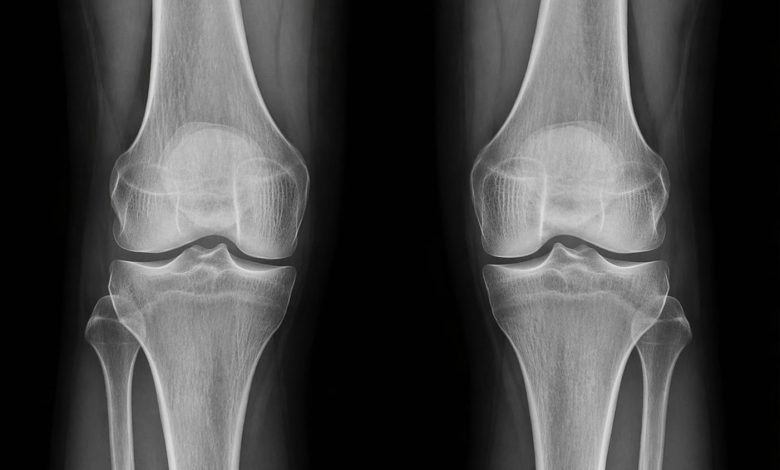

Исследователи из Стэнфордского университета сделали важный шаг к созданию методов лечения остеоартрита — распространенного заболевания, которое ограничивает подвижность и вызывает хроническую боль у пожилых людей. В ходе экспериментов на мышах ученые выявили ключевую роль белка 15-PGDH, количество которого увеличивается с возрастом. Этот белок препятствует работе молекул, отвечающих за восстановление тканей и снижение воспаления, что напрямую связано с разрушением суставного хряща.

В своих тестах на старых мышах ученые использовали ингибитор (блокатор) белка 15-PGDH. Результат превзошел ожидания: истонченный с возрастом коленный хрящ начал утолщаться и восстанавливаться. Аналогичные испытания на молодых мышах с травмами показали, что ингибитор защищает суставы от последствий посттравматического остеоартрита. Когда исследователи вызвали у грызунов повреждение, эквивалентное разрыву передней крестообразной связки у человека, и применили терапию, болезнь не развилась по обычному сценарию.

У мышей, получивших лечение, походка стала более устойчивой, и они охотнее наступали на травмированные лапы, что свидетельствует об уменьшении боли и улучшении физического состояния. Важно, что тот же эксперимент был проведен на образцах тканей человека, взятых у пациентов после операции по замене коленного сустава. Результаты подтвердились: в человеческом хряще также были зафиксированы явные признаки регенерации — он стал более жестким, а признаки воспаления уменьшились.

Ортопед Нидхи Бхутани отметил, что механизм воздействия поразителен и меняет представление о регенерации тканей. По словам ученого, существующие в хряще клетки просто меняют характер экспрессии своих генов, и воздействие именно на них может иметь гораздо больший клинический эффект. Хотя предстоит еще много работы, это открытие может привести к созданию эффективных методов лечения, которые позволят обратить вспять повреждения, вызванные артритом, и в будущем отказаться от операций по замене тазобедренных и коленных суставов.